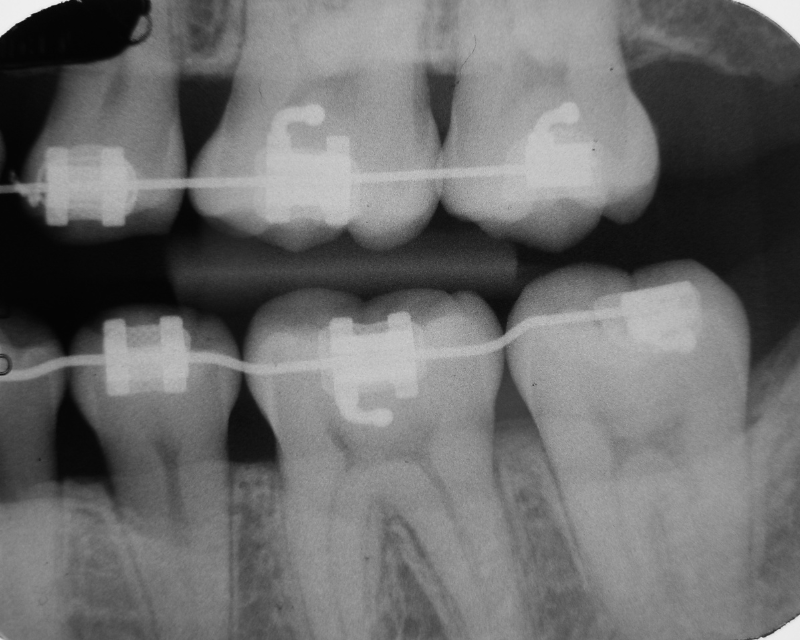

Braces, one of the most common orthodontic tools, work by applying gentle pressure to shift teeth into optimal positions. During this process, patients often become more vigilant about their oral hygiene routines, as the hardware makes it evident when cleaning is inadequate. Similarly, clear aligners like Invisalign offer orthodontic treatment benefits by being removable, encouraging better habits without the permanence of traditional braces. Aligners and oral hygiene go hand in hand because users must remove them before eating or drinking anything other than water, minimizing exposure to decay-causing substances.

Studies published in the Journal of Clinical Orthodontics show that patients undergoing orthodontic care experience a notable decrease in plaque accumulation post-treatment. This is because aligned teeth facilitate better access for dental tools, ensuring comprehensive cleaning. Preventing cavities with braces involves not only the alignment but also the educational aspect, orthodontists guide patients on tailored hygiene practices, reinforcing long-term habits that sustain decay prevention.

Consider the case of overlapping incisors: Food debris gets trapped, and bacteria thrive in these sheltered spots. A 2023 study from the International Journal of Dentistry found that individuals with moderate to severe malocclusions had up to 40% higher rates of caries compared to those with straight teeth. Preventing tooth decay with orthodontics mitigates these risks by creating a more uniform tooth surface. Straight teeth and decay reduction are evident in post-treatment scans, where patients show healthier enamel and reduced bacterial colonies.